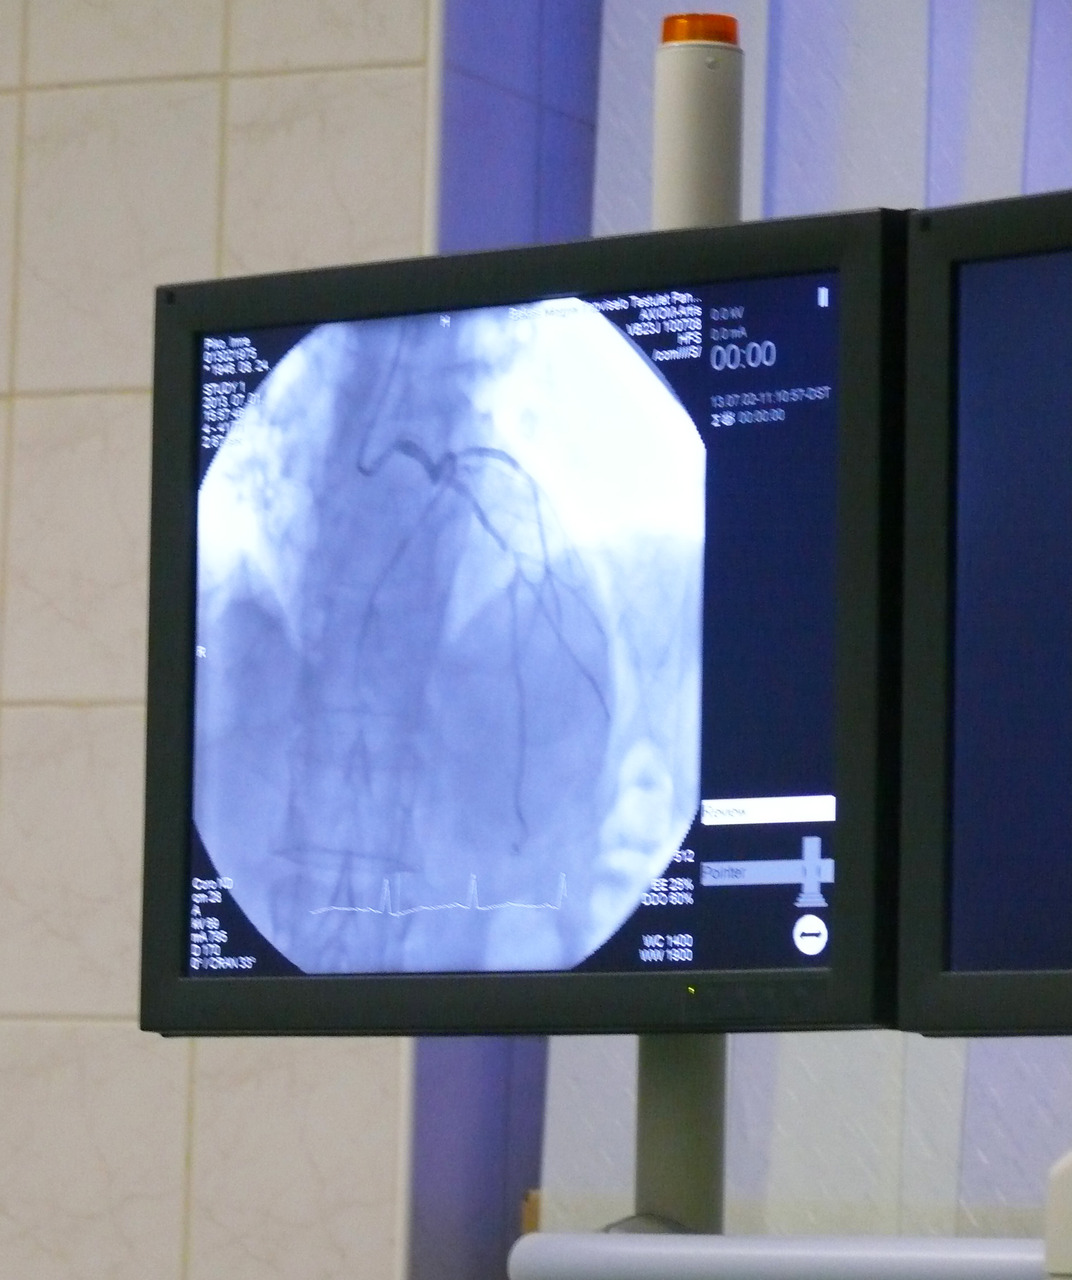

- Július 1-jétől a Békés megyében szívinfarktust szenvedett betegek szívkatéteres ellátása Gyulán történik, ugyancsak alkalmas a laboratórium azon betegek ellátására, akiknél az előzetes vizsgálatok jelentős szívkoszorúér szűkületre utaltak. Ilyen esetben a beszűkült koszorúér szakasz katéteres tágítása történik. A szívkatéteres vizsgálat, illetve beavatkozás sürgős és tervezett esetben is hasonlóan indul a beteg teljes körű tájékoztatását követően. A vizsgálat során a beteg ébren van, steril műtői textíliával letakarva fekszik egy speciális vizsgálóasztalon. A pulzusok vizsgálatával az orvos megkeresi a legmegfelelőbb behatolási kaput, ahol érzéstelenítés után egy rövid műanyag csövet vezet be. Ezt követően speciális görbületű, vékony hosszú csövet (katétert) vezetnek fel egészen a szívet ellátó koszorúerek szájadékáig. A szívkoszorúerekbe kontrasztanyagot fecskendezve speciális, kis sugárzást kibocsátó átvilágító készülékkel az egész koszorúér megjelenik a vizsgáló monitorján. Azonnal látszik, hogy szívinfarktus esetén melyik koszorúér melyik szakaszán van vérrög. Tervezett esetben végzett szívkatéteres vizsgálat során a koszorúéren áramlást csökkent érszűkületet keresnek. Mindkét esetben beavatkozásra van szükség, így a diagnosztikához használt katétert lecserélik, hogy a szükséges eszközt le tudják juttatni a koszorúér belsejébe. Szívinfarktus esetén a vérrög leszívását követően az esetek nagy többségében fémhálóból szőtt csövecskét helyeznek el az érben. Az infarktusos beteg ezt követően a kórház kardiológiai őrzőjébe kerül további gyógykezelés céljából. A betegek állapotuktól függően már másnap elhagyhatják a kórházat - avatott be a részletekbe Jambrik Zoltán főorvos.

A beruházás eredményeként az ország legújabb, legmodernebb szívkatéteres laboratóriuma kerül a Békés megyei betegek szolgálatába.